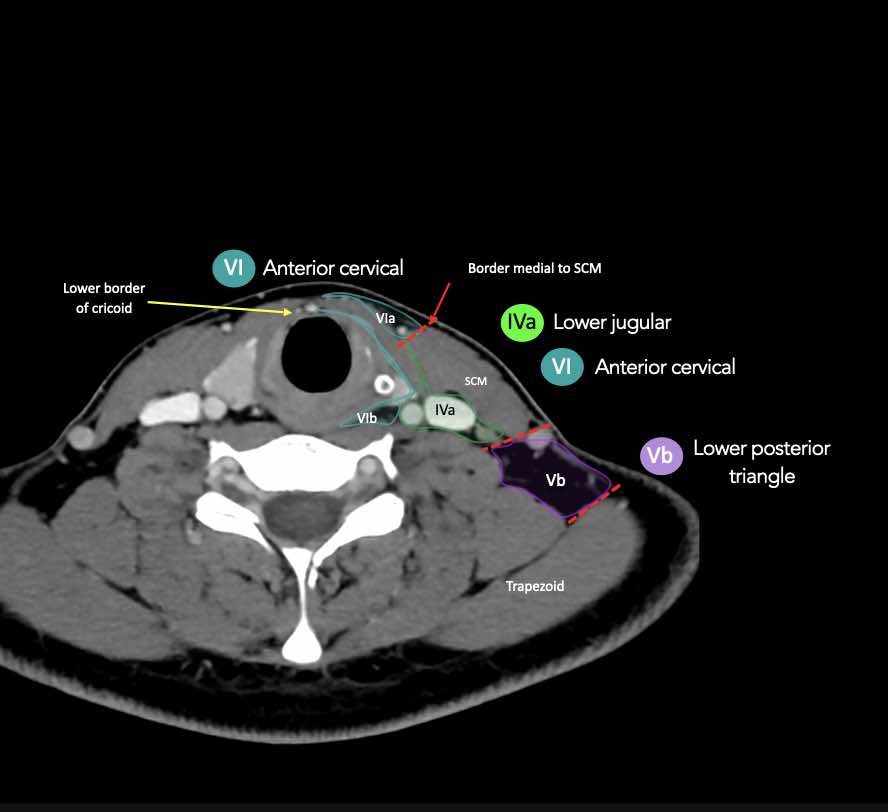

CT Scan Mặt Cắt Ngang (Axial CT)

Các lát cắt CT mặt phẳng ngang tương ứng với hình minh họa tổng quan.

Các lát cắt CT mặt phẳng ngang với hình ảnh chi tiết hơn.

Nhấp vào hình ảnh để phóng to.

IV – Tĩnh mạch cảnh dưới và hố thượng đòn trong

Ranh giới giữa tầng IVa và IVb được xác định tùy ý tại vị trí 2 cm phía trên khớp ức đòn.

Tầng IVa

Các hạch này có nguy cơ chứa di căn từ các ung thư hạ hầu, thanh quản, tuyến giáp và thực quản cổ.

Hiếm gặp hơn, di căn từ khoang miệng trước có thể biểu hiện tại vị trí này với tổn thương hạch gần tối thiểu hoặc không có.

VI – Cổ trước

Tầng này chứa các hạch tĩnh mạch cảnh trước nông (tầng VIa) và các hạch sâu hơn bao gồm hạch trước thanh quản, trước khí quản, cạnh khí quản và hạch thần kinh thanh quản quặt ngược (tầng VIb).